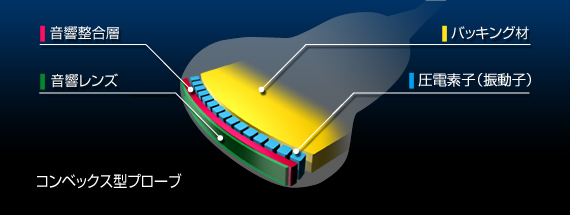

TOSHIBA PLE-705S型 リニア式電子スキャンプローブ エコー 超音波診断装置 東芝の詳細情報

カテゴリビューティー、ヘルスケア救急、衛生用品その他状態傷や汚れあり(詳細)■商品名:PLE-705S型 リニア式電子スキャンプローブ